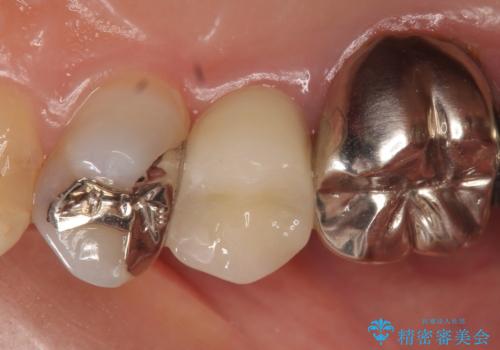

診査の結果神経を保存するのは困難だったため、根管治療を行った後、オールセラミッククラウンによる補綴を行いました。

今回用いたオールセラミッククラウンはジルコニアフレームという白い素材の上にセラミックを盛っているため、審美性が非常に高いのが特徴です。

また、ジルコニアは人工ダイヤモンドの材料にも使われているほど高い強度を持っており、そのためオールセラミッククラウンは審美性だけでなく、奥歯やブリッジの補綴も可能とするクラウンです。